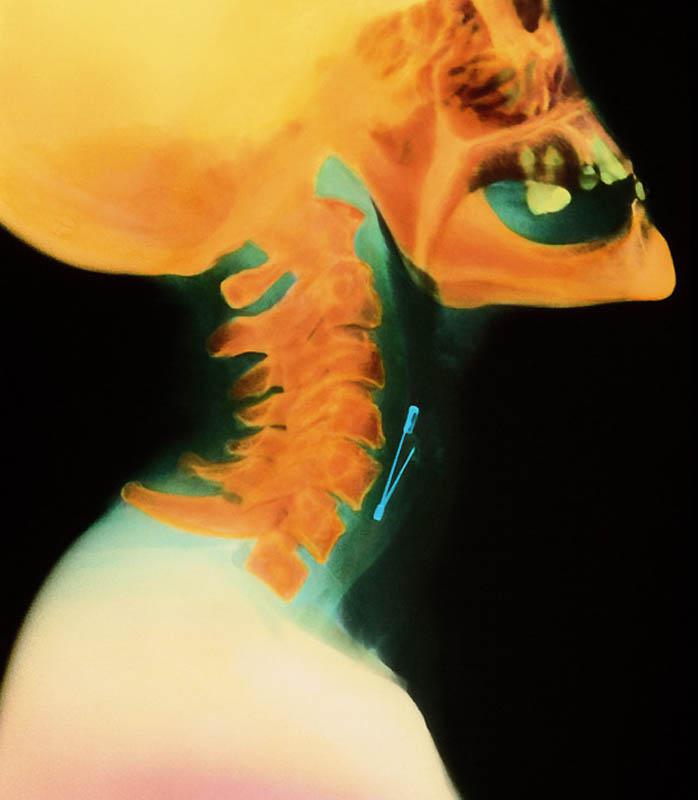

Булавка в горле женщины.